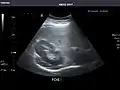

Aorta